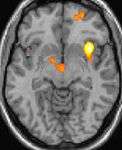

Positron emission tomography (PET) shows brain areas being activated during pain

Some theories suggest that CH attacks may be related to dysfunction of the hypothalamus, this may explain why cluster headaches frequently occur around the same time each day, and during a particular season. One of the functions of the hypothalamus is regulation of the biological clock. Metabolic abnormalities have also been reported. Positron emission tomography (PET) scans indicate the brain areas which are activated during attack only, compared to pain free periods. These pictures show brain areas which are active during pain in yellow/orange color (called "pain matrix"). The area in the center (in all three views) is specifically activated during CH only. The bottom row voxel-based morphometry (VBM) shows structural brain differences between individuals with and without CH; only a portion of the hypothalamus is different.[23]